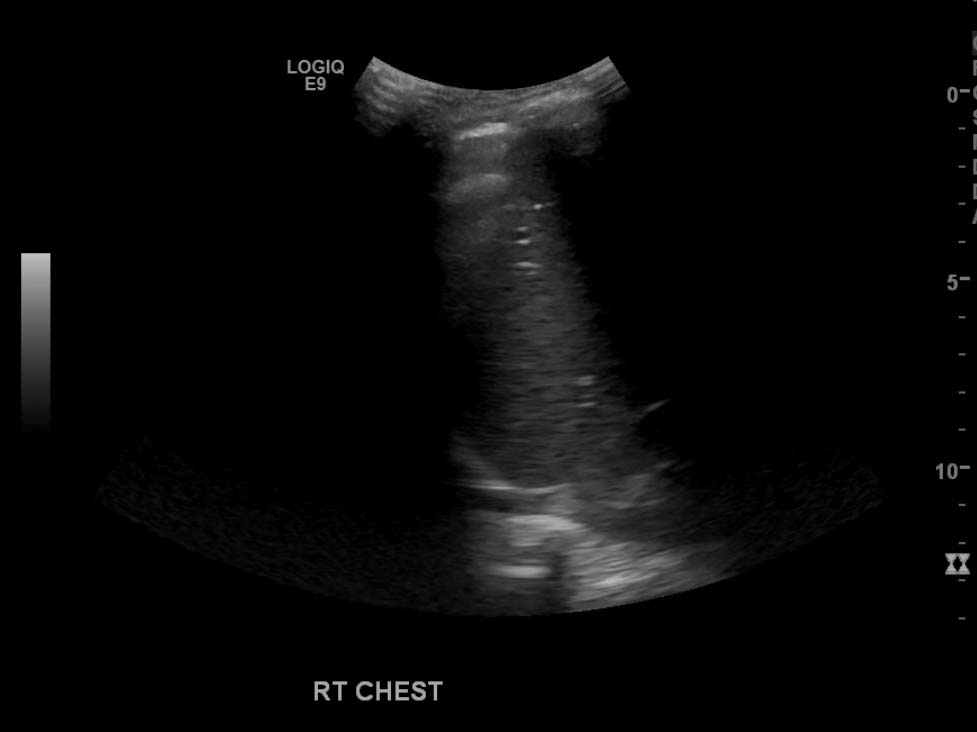

- Large, complex, multiseptated left pleural fluid collection

- No right pleural fluid collection identified

Large, complex, multiseptated left pleural fluid collection with adjacent airspace consolidation, concerning for pneumonia and empyema. No discernible right pleural effusion.

- Simple/transudative pleural effusions should be anechoic on ultrasound

- Worry about a complicated effusion (which may represent empyema, hemothorax, or malignant effusion depending on the clinical scenario) if the fluid collection has hyperechoic areas or if it contains internal septations